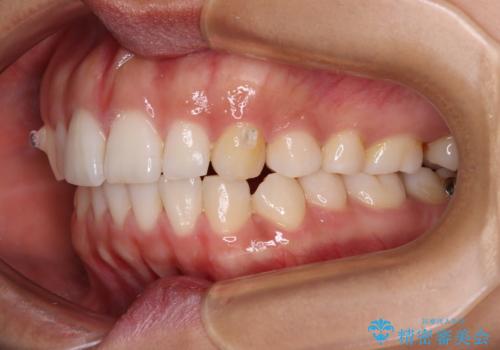

【モニター】突出した前歯 補助装置を併用したインビザライン矯正

- 上下前歯が非接触となり、前方に突出していることを気にして来院された患者様です。

咬合力が強く、全体的に歯がすり減っているため、インビザライン単独での上顎歯列移動は困難と判断し、補助装置により上顎歯列を後方移動させ、その後インビザラインにて仕上げていくこととしました。

補助装置なしでも改善できる可能性はありましたが、補助装置で確実性を上げ、短期間できっちりと仕上げることができました。